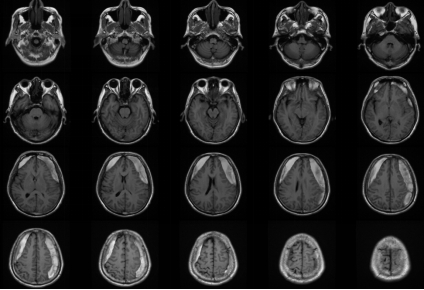

近期,我科完成了一例慢性硬膜下血肿手术。该患者男性,63岁,是因为“摔伤头部半年,记忆力下降,思维迟钝大约20天” 在当地医院就诊,行颅脑CT提示双侧额颞顶部慢性硬膜下血肿,脑疝,CT片可见慢性血肿有很多分隔。当地医院医生建议患者分二次行双侧开颅手术,清除硬膜下血肿,创伤很大,手术后需要住ICU,而且住院时间很长,费用高。患者家属犹豫不决,担心手术风险,于是带着CT片到我科门诊咨询。门诊孟主任阅片后告知家属,我科可以通过神经内镜微创手术治疗慢性硬膜下血肿,可以一次手术,手术创伤小,风险低,费用少,住院时间短,大约10天左右就可以出院,而且手术后不需要住ICU,于是家属当天下午就驱车带患者来我科住院。管床医生涂医生仅用一天时间就完成全部术前检查,第二天就安排了手术。手术中通过神经内镜观察到慢性硬膜下血肿有很多的分隔及纤维组织,与可自行流出的液态慢性血肿相比,该患者需通过吸引器反复仔细吸除血肿分隔及纤维组织,同时反复盐水、双氧水冲洗,避免血肿残留及复发。手术过程很顺利,术后患者清醒,无任何神经功能障碍及并发症,手术后10天患者治愈出院,在后期随访观察中,未见慢性血肿复发。

神经内镜血肿清除术